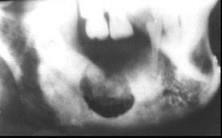

在X线片上能看到中央性颌骨骨髓炎骨质广泛破坏时间一般是 ( ) A.3周以后 B.2~3个月 C.1~2周 D.1周 E.2个月

问题 在X线片上能看到中央性颌骨骨髓炎骨质广泛破坏时间一般是 ( )

选项 A.3周以后 B.2~3个月 C.1~2周 D.1周 E.2个月

答案 A